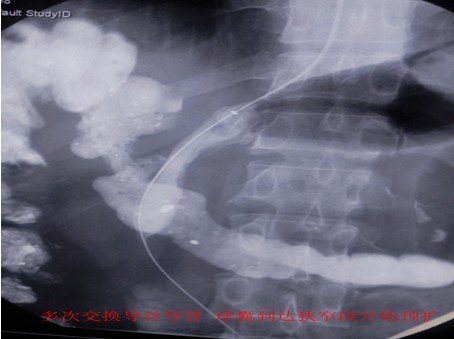

择日二次手术,在长达3小时不懈努力后,导管导丝终于通过,球囊扩张狭窄段后,支架输送装置顺加硬导丝通过狭窄段时受阻,无法通过,达到欲释放位置。放弃手术,择日更换更加柔软支架,再次手术。

择日“三进攻” 支架顺利植入狭窄部位,上下端“蘑菇头”膨胀良好,上端“蘑菇头”卡位良好。

三天后胃肠造影复查,支架膨胀良好,无移位,造影剂顺利通过支架进入十二指肠。